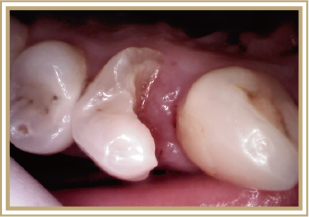

そこで今回、一般歯科医院の保険医としてわたしが日常的に対応する症例を中心に、ガスレーザーの特性を応用することが最適と考えて治療を行った臨床記録の一部を供覧させていただきます。雑然とした画像で申し訳ありませんが、患者さんに了解を得た動画や写真を参考資料として解説させていただきます。